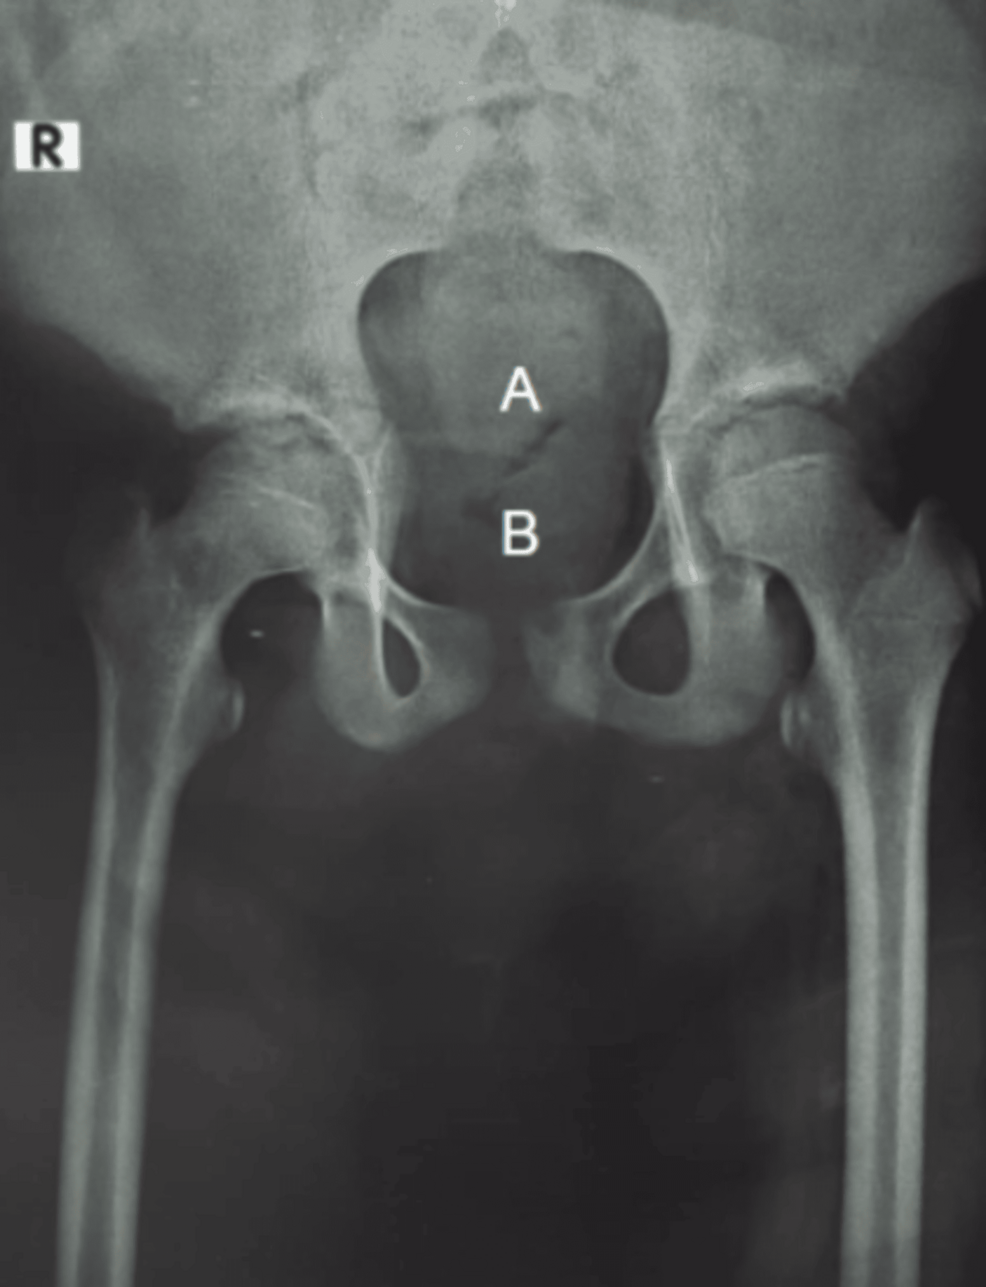

Sacral Agenesis Type II: Delayed Diagnosis in Low-Resource Setting

The presentation of Sacral Agenesis, a rare congenital disorder, at age 12 underscores a concerning pattern: delayed diagnosis. This delay, frequently observed in areas with limited access to advanced diagnostics, isn’t just a matter of inconvenience. It can lead to severe and irreversible health complications, drastically impacting quality of life. This situation highlights the urgent need to address the underlying reasons for delayed identification, which extend beyond just the availability of resources.